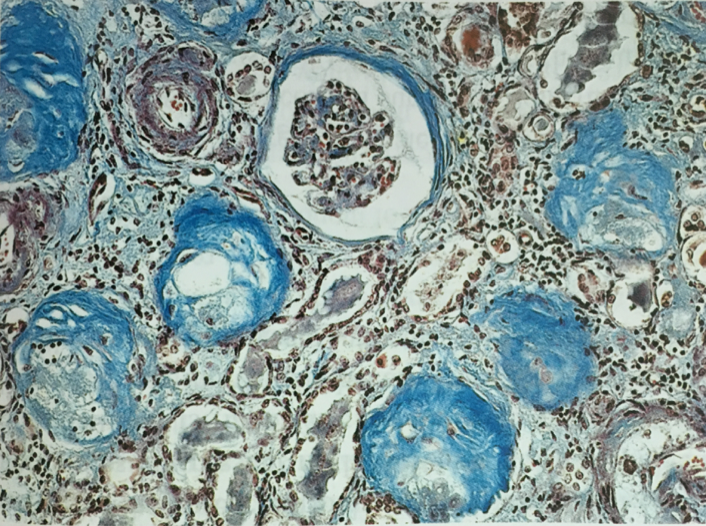

9. 硬化性肾小球肾炎(sclerosing glomerulonephritis)

硬化性肾小球肾炎(sclerosing glomerulonephritis)不是一个独立的肾小球肾炎病理类型,而是许多类型肾小球肾炎的终末阶段。病变特点是大量肾小球硬化,肾小管萎缩、消失,间质纤维化。起始病变的类型多不能辩认。

(1) 病理变化

大体:两侧肾脏对称性固缩,表面呈微小颗粒状,故称之为颗粒性固缩肾(granular nephrosclerosis)。切面观,皮质变薄,皮髓质分界不清。

光镜下:大量肾小球硬化、玻璃样变(超过全部肾小球的50%)。肾小球中央部分变为无细胞、嗜伊红、PAS阳性之玻璃样小体,周围部分纤维化(如下图)。少数肾小球结构残存。硬化肾小球所属肾小管萎缩、消失、使玻璃样变的肾小球相互靠拢集中。残留肾单位常呈代偿性肥大,肾小球体积增大,肾小管扩张。间质纤维组织增生并有大量淋巴细胞、浆细胞浸润。间质内小动脉硬化,管壁增厚,管腔狭窄。

(肾小球纤维化及玻璃样变,所属肾小管萎缩、消失。间质纤维化伴炎细胞浸润。)

(纤维被染成了蓝色)